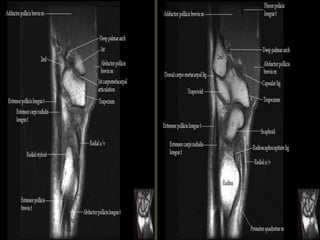

Pronator quadratus.